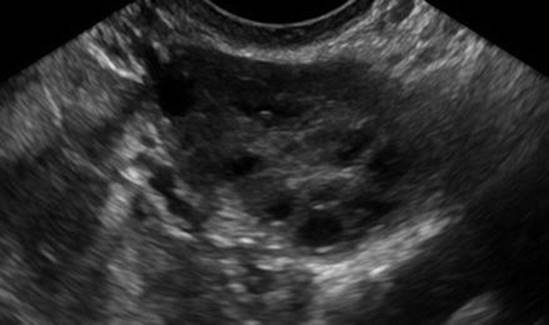

Pelvic ultrasounds in patients with PCOS will reveal multiple peripheral follicles and an overall volume greater than 10 mL (Fig. 4.12); enlargement is usually bilateral, but can be unilateral [68]. The ovarian stroma may also be increased and echogenic, though use of oral contraceptive pills may normalize the appearance of the stroma [69]. Urgent intervention is not indicated, except in cases of suspected torsion; patients can be followed by gynecologists in the outpatient setting for management of oligo-ovulation and hirsutism, as needed.

Fig. 4.12

Polycystic ovarian syndrome. Transvaginal ultrasound of a 21-year-old patient with PCOS reveals several small, peripherally located follicles with a “string of pearls” appearance